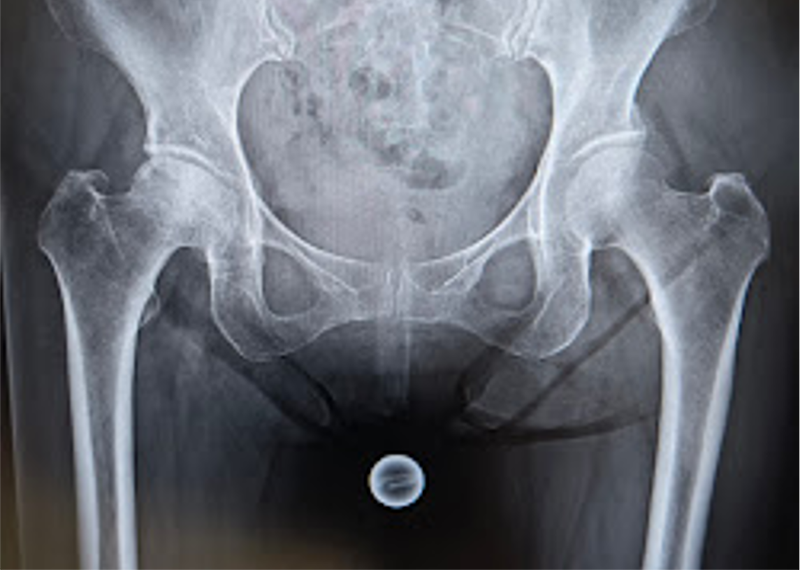

〈手術前のレントゲン〉